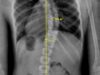

اعوجاج العمود الفقري عند الأطفال يُعد اعوجاج العمود الفقري (الجنف) من أكثر مشكلات العظام شيوعًا عند الأطفال والمراهقين، وغالبًا ما يثير القلق لدى الأهل عند سماع التشخيص لأول مرة. ولأن الفهم الصحيح لأسباب الاعوجاج

تمارين علاج طبيعي فعّالة لاعوجاج العمود الفقري عند الأطفال اعوجاج العمود الفقري، أو ما يُعرف طبيًا باسم الجنف، هو من المشكلات الشائعة التي قد تظهر لدى الأطفال أو المراهقين، خاصة خلال فترات النمو السريع.